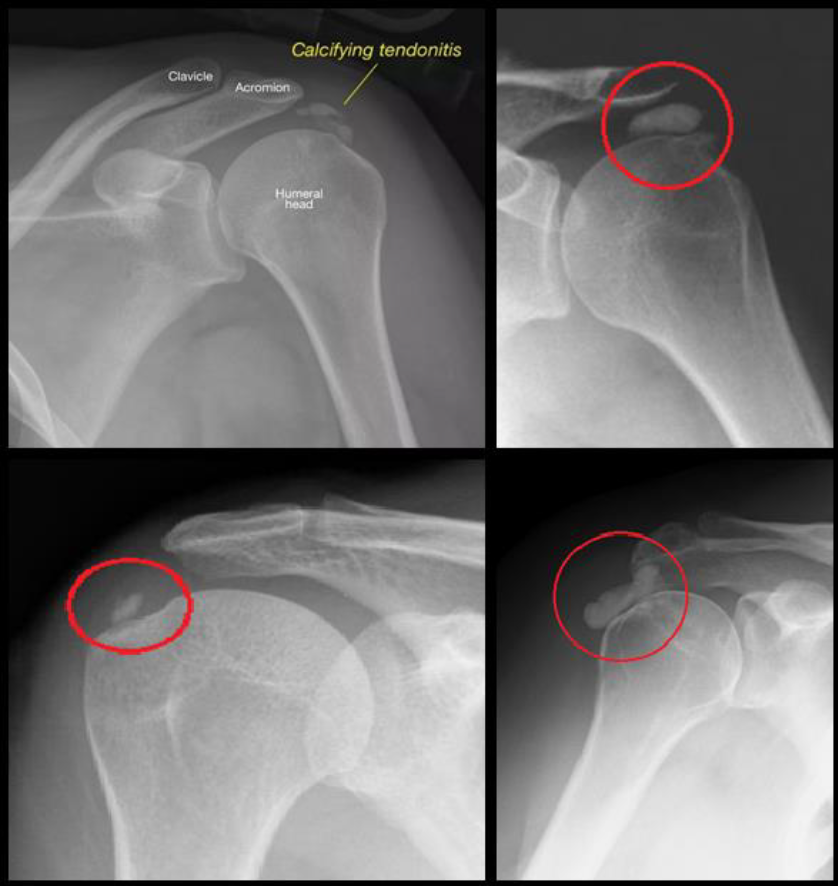

A calcium deposit accumulates in one of the tendons of the shoulder. The cause is unknown and not related to injury, diet or osteoporosis. The most common group of patients are female, 40-50 years of age, but other age groups and males can also be affected. Calcifications can have a paste-like consistency or a hard deposit in the shoulder.

Calcifications can become bigger and although this is a painful condition, it does not damage the shoulder in any way and conservative management (non-operative) is in order if the patient can live with the pain.

Arthroscopy (“key-hole surgery”) is done. There are two types of calcifications – Hard and soft Calcifications. The hard calcification is like a crystal so it is hard and the soft calcification is paste-like. Depending on the classification, sometimes the muscle needs to be cut in order to remove the calcifications. When the Rotator Cuff Muscle is destroyed due to the calcification it must then be repaired as well.